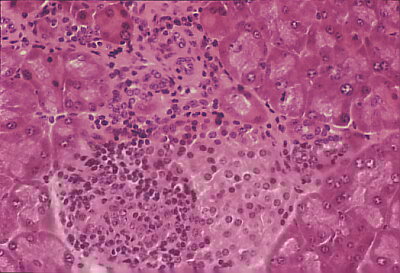

正常ラットを基礎集団として選抜交配をして糖尿病ラットを作るのに成功した頃、米国の実験動物飼育場(B B Lab.)では重症の糖尿病になるラットがみつかり、膵島にはリンパ球の浸潤がみられ膵島炎が起こっていることが報告された。

NODマウスは雌は生後30週齢までにほぼ80〜100%が糖尿病となり雄は40%しか糖尿病にならない。佐藤譲博士らはOK432を生後4週齢から25週齢まで毎週1回1単位腹腔内注射すると、未処置雌マウスでは80%が糖尿病を発症したのに対し、注射群では発症は0%であった。NODマウスの膵島炎は生後4週齢から出現し始めたので、4-10週の間にOK432を注射するのが膵島炎の抑制に有効であることが分かった。膵島炎が完成し糖尿病が発症してからではOK432は全く効果がないことも明らかになった。